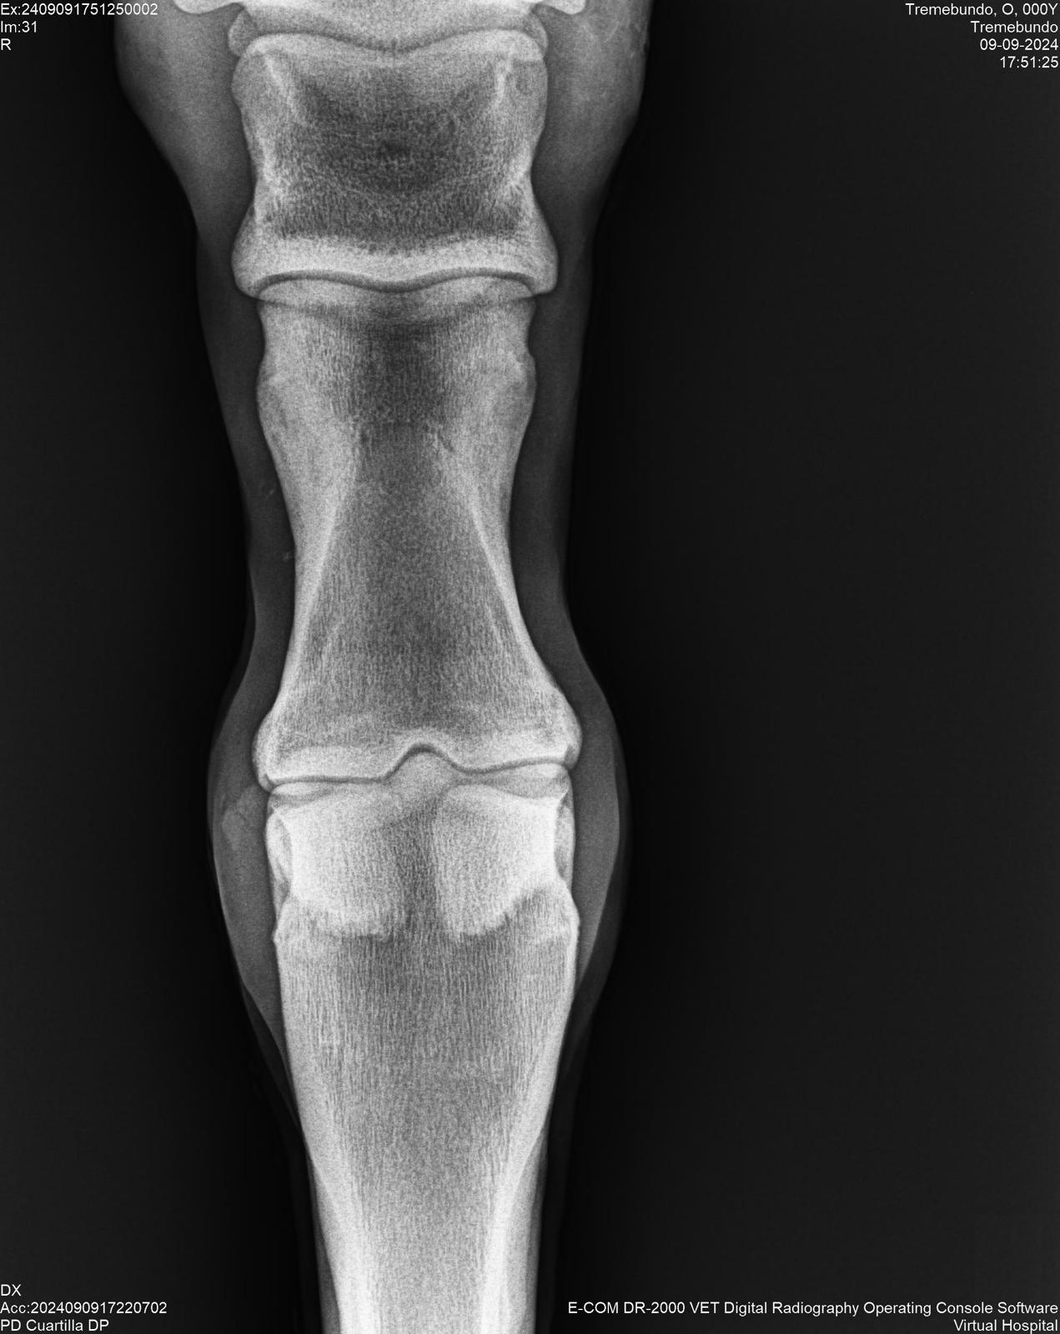

LOTE 37, TREMEBUNDO

Identificador: #291140-

Generacion 2022